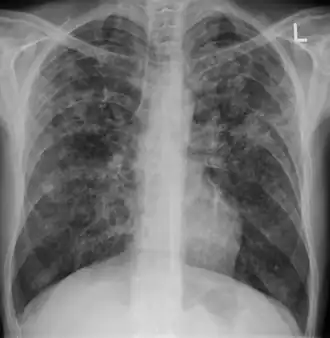

A case of miliary tuberculosis in an 82-year-old woman:

-

X-ray, 22 days after onset, showing extensive bilateral reticulo-nodular infiltrates -